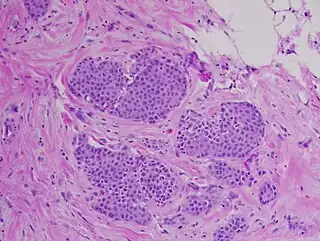

Carcinoma lobulillar 'in situ', tinción hematoxilina-eosina, 20x | ||

El CLIS es una proliferación sólida y oclusiva de los lobulillos y otros conductos perilobulillares. Los acinos de las glándulas se ven dilatados y ocupados por células pequeñas y por lo general uniformes, siendo pleomórficas solo en la afectación ductal del carcinoma, es decir, cuando aparece en los conductos mamarios. Estas células no han invadido los tejidos más profundos del seno, ni se han propagado a otros órganos del cuerpo.[2] Rara vez se ve necrosis o calcificación y de aparecer ocurre en las etapas más avanzadas de la enfermedad.[4]